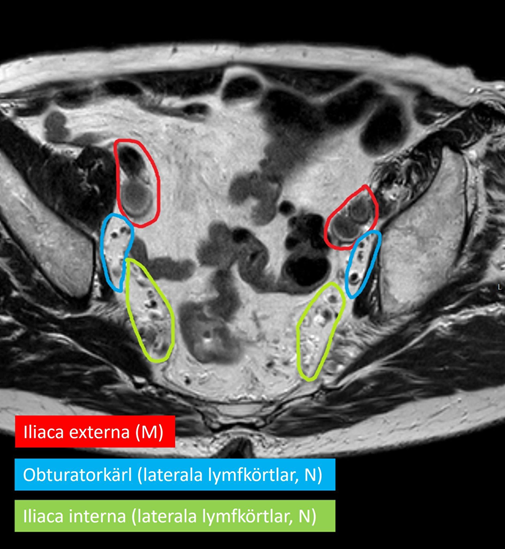

Regionala lymfkörtelstationer (för N-stadieindelning) för koloncancer är lokaliserade i mesokolon. Regionala lymfkörtelstationer för rektalcancer är lokaliserade i mesorektum, i mesokolon tillhörande distala sigmoideum inklusive längs vena rektalis superior samt i obturator- och iliaca interna-regionen. Lymfkörtlar i obturator- och iliaca interna-regionen benämns laterala regionala lymfkörtlar. Lymfkörtelmetastaser längs aorta, iliaca externa och iliaca communis är inte regionala utan klassificeras som fjärrmetastaser och ingår i M‑staging. Inguinala lymfkörtlar betraktas oftast som fjärrmetastaser, men kan vid mycket lågt sittande cancer som engagerar analkanalen utgöras av regionala lymfkörtlar 52.

Figur 5. MRT-bild som visar lymfkörtlar vid iliaca externa (röd), i obturatoriuslogen (blå) och vid iliaca interna (grön)

År 2017 publicerade ESGAR (European Society of Gastrointestinal and Abdominal Radiology) rekommendationer för utredning av rektalcancer inklusive bedömning av regionala lymfkörtlar 53. Uppdatering av riktlinjerna pågår (2024). Däremot har en internationell expertgrupp publicerat konsensus för hur riktlinjer för MRT av rektaltumörer ska tolkas och användas 54. Regionala mesorektala lymfkörtlar vid rektalcancer bedöms utifrån både morfologi och storlek. Instruktioner för preterapeutisk bedömning finns på SFMR:s webbplats. Regionala laterala lymfkörtlar längs obturatorkärl och iliaca interna-kärl bedöms däremot enbart utifrån storlek. Laterala regionala lymfkörtlar med kortaxeldiameter ≥ 7 mm före neoadjuvant behandling är kopplade till hög risk för metastaser och rapporteras därför som metastasmisstänkta. Någon säker nedre storleksgräns för vilka lymfkörtlar som är friska finns inte.

En nyligen publicerad studie 55 har visat att utöver lymfkörtelstorlek har även antalet metastasmisstänkta laterala lymfkörtlar betydelse, liksom deras morfologiska utseende. Dessa data är ännu inte bekräftade men kan komma att påverka framtida riktlinjer för bedömning av laterala lymfkörtlar. Bedömning av laterala regionala lymfkörtlar är alltså svårt och det är omöjligt att utifrån bilddiagnostiska fynd säkert differentiera friska lymfkörtlar från lymfkörtelmetastaser. Därför bör alla laterala lymfkörtlar med kortaxeldiameter ≥ 4 mm rapporteras som ett observandum inför eventuell strålbehandling och uppföljande bilddiagnostik samt bli föremål för diskussion på MDK 56.